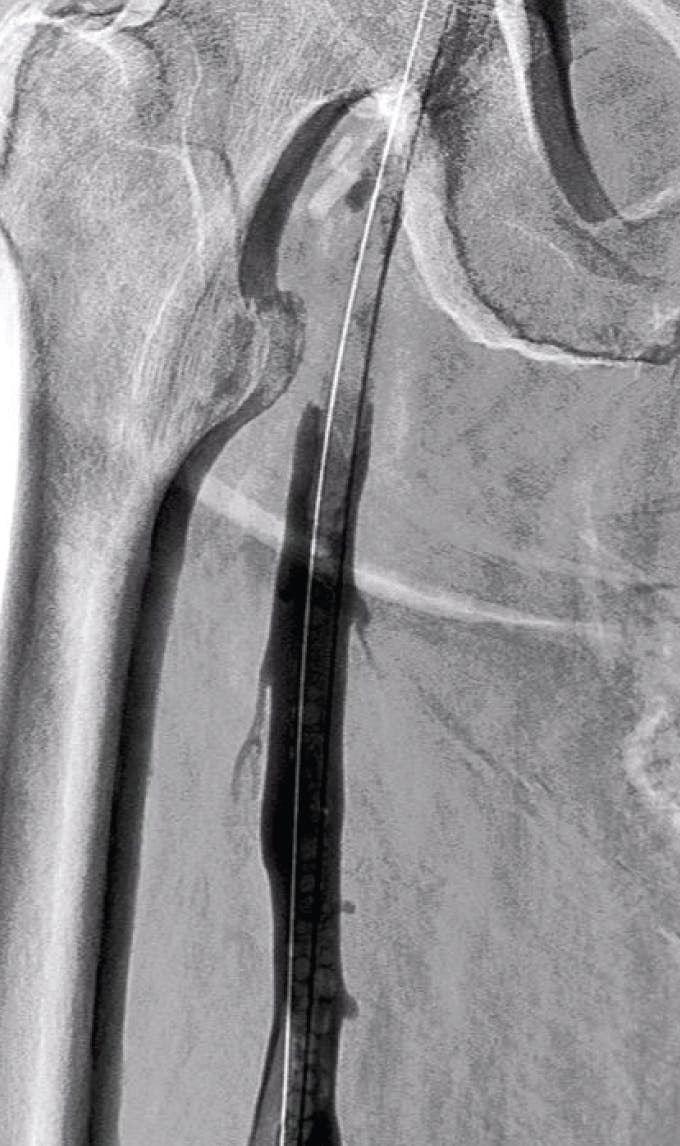

Figure 1. Preprocedural venogram.

PROCEDURAL DETAILS

The patient was placed on the table in the prone position. Access was then gained in the popliteal vein and a 16-F, 13-cm Flexor Check-Flo Introducer (Cook Medical) was placed. The Lightning Flash catheter was pulled and advanced through the sheath until the tip was at the face of the occlusion. Once at the face of the thrombus, the flow switch was flipped on to initiate aspiration power. On the first pass, macromovements were utilized to advance the tip of the catheter past the occlusive lesion. Ensuing this run, images were obtained. Venography confirmed that 60% of the clot burden was cleared from the initial pass. A few additional passes with the catheter were performed until complete thrombus resolution was achieved in the iliofemoral segment (Figure 2 and Figure 3), with a total aspiration time of 12 minutes.

Figure 2. Final venogram.

Figure 3. Clot extracted after use of the Lightning Flash.

CONCLUSION

Lightning Flash successfully reduced thrombus burden and did so in an efficient manner. This is especially noteworthy considering the occlusive state and the volume of thrombus present in this particular case. Additionally, the atraumatic design of the catheter and ease of use of the system resulted in a higher level of comfort for the patient.